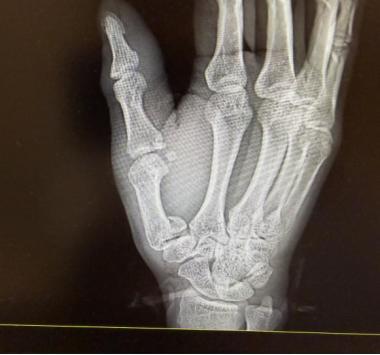

拍片結果印證了劉醫生的判斷,李先生右手第一掌骨、第一近節指骨基底部都骨折了。劉醫生爲他的傷口做了清創縫合,隨後骨科醫生也及時介入,做了臨時石膏固定,後續李先生還得住院擇期手術。說起這事,李先生滿是懊惱,不僅自己受了罪,還把兒子嚇得大哭,給孩子留下了心理陰影。